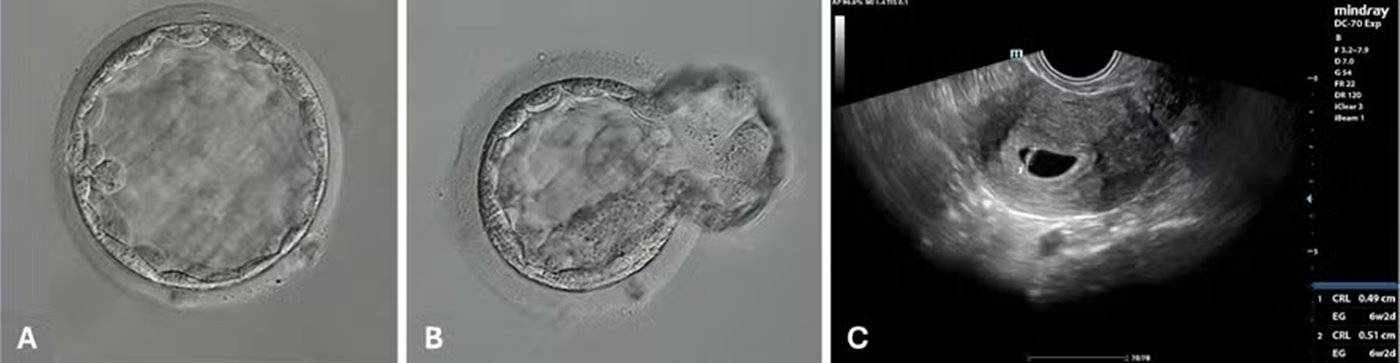

O parto bem-sucedido ocorreu com uma mulher de 40 anos, tratada com óvulos doados após uma tentativa anterior de FIV sem sucesso. No estudo, cinco óvulos foram fertilizados com ICSI automatizada e três com o método manual, para comparação. O sistema foi instalado na clínica Hope IVF México, e operadores em Guadalajara e Nova York controlaram remotamente as 23 etapas do processo para cada óvulo, totalizando 115 ações.

O procedimento automatizado levou, em média, 9 minutos e 56 segundos por óvulo — um pouco mais que a ICSI manual, devido ao caráter experimental. A expectativa é reduzir esse tempo futuramente.

Quatro dos cinco óvulos do grupo automatizado foram fertilizados com sucesso, assim como os três do grupo manual. Um dos embriões gerados remotamente de Nova York evoluiu até o estágio de blastocisto e foi transferido após vitrificação e descongelamento.

GESTAÇÃO

A gestação seguiu normalmente e resultou no nascimento de um bebê saudável do sexo masculino. Embora novos estudos sejam necessários, os pesquisadores consideram o caso um avanço importante rumo à automação total da fertilização in vitro.